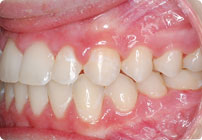

Masculino

Antes

Despues

Caso: 11 años

Adolescente: Clase II

Mordida Cruzada Posterior

Sin extracción

Sin uso de expansores

6 alambres superiores

5 alambres inferiores

Sin uso de elásticos

Retenedores: Interior Fijo de TMA y Hawley en superior

Tiempo de tratamiento: 14 Visitas